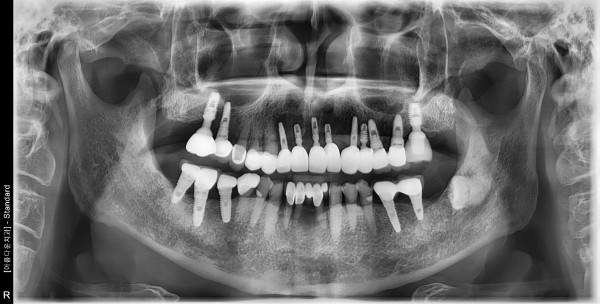

70대 남성 임플란트 식립